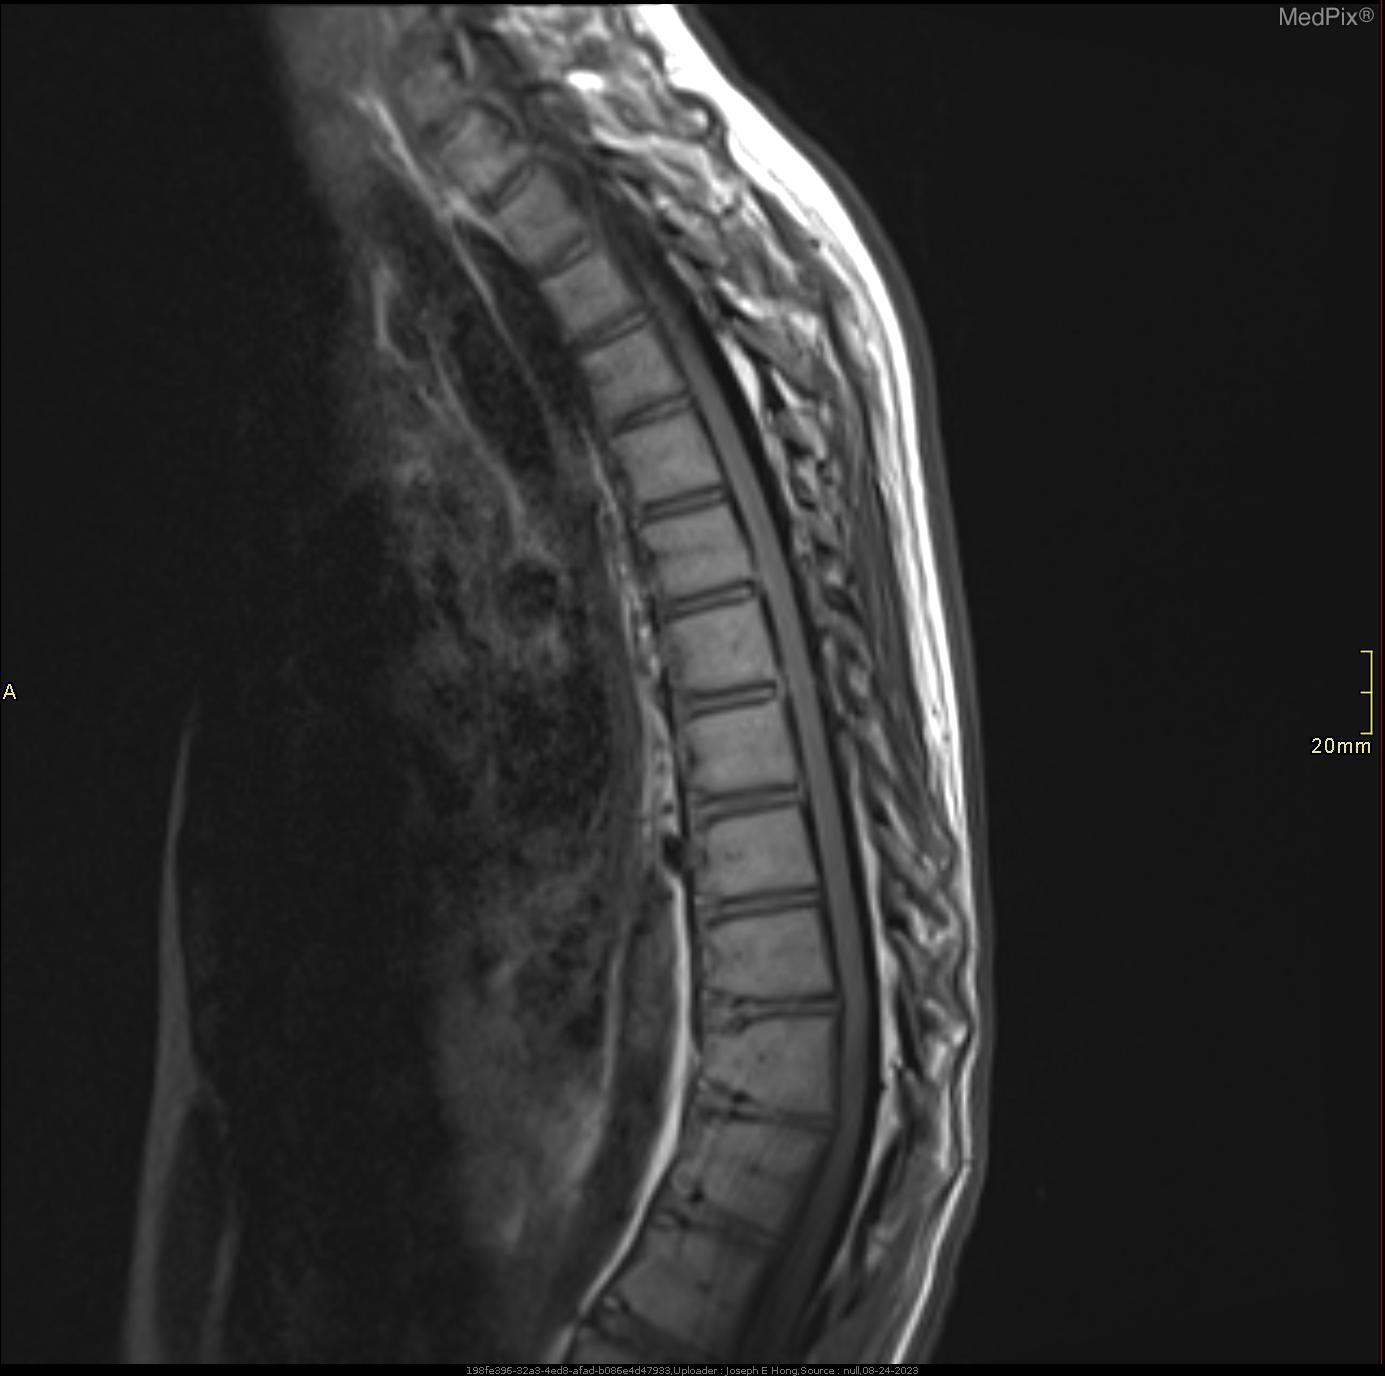

Kyphosis is a forward curvature of the upper spine. Some rounding is normal but kyphosis generally refers to an increased rounding of 40 to 45 degrees or more. This condition is often called hunch back. Kyphosis may be due to degenerative diseases, osteoporosis with compression fractures of the vertebrae, developmental problems or trauma to the spine. This condition can affect all ages, cause few problems in mild cases but also be so severe it can affect your breathing/lungs, nerves, organs, etc. Physical Therapy can help with postural education, strengthening and stretching exercises and ergonomic tips to prevent the condition from worsening.